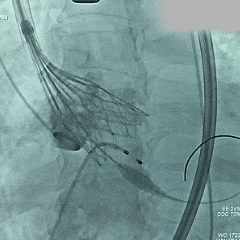

脱钩释放

脱钩后,瓣膜无位移

造影评估,瓣膜深度可,无瓣周漏

左头观察,腰征明显,锚定稳定